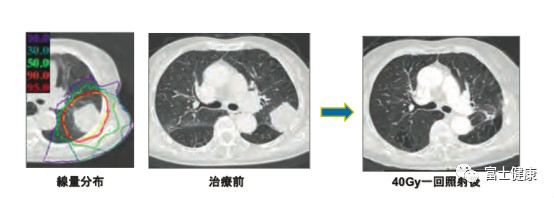

現(xiàn)在QST醫(yī)院,患者人平均照射次數(shù)是12次(3周),為普通放療次數(shù)的一半以下。I期肺癌或肝癌,一次或兩次照射即可完成治療。前列腺癌或胰腺癌采用3周12次照射法,F(xiàn)在所有3周12次照射治療都采用掃描照射法。

圖5 .肺癌1次照射(71歲女性)鱗癌(T2N0M0)40Gy1次照射